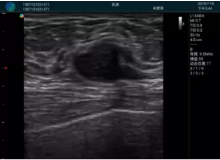

腺體內(nèi)部清晰顯示一低回聲塊影,形態(tài)不規(guī)則,邊界模糊,邊緣呈毛刺狀,內(nèi)部見砂礫樣鈣化

M20引導(dǎo)下穿刺活檢術(shù)

M20引導(dǎo)下平面內(nèi)穿刺取出的腫塊組織